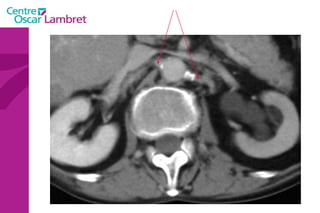

Piége: Piliers du diaphragme

Piége: Piliers du diaphragme Coupes natives  reconstructions

PIEGES Insertions diaphragmatiques